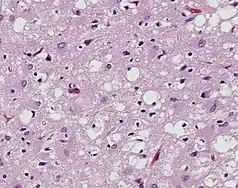

Prions are misfolded proteins that transmit their abnormal folding pattern to other copies of the protein without using nucleic acids. Besides obtaining prions from others, these misfolded proteins arise from genetic differences, either due to family history or sporadic mutations.[21] Plants uptake prions from contaminated soil and transport them into their stem and leaves, potentially transmitting the prions to herbivorous animals.[22] Additionally, wood, rocks, plastic, glass, cement, stainless steel, and aluminum have been shown binding, retaining, and releasing prions, showcasing that the proteins resist environmental degradation.[23]

Prions are best known for causing transmissible spongiform encephalopathy (TSE) diseases like Creutzfeldt–Jakob disease (CJD), variant Creutzfeldt–Jakob disease (vCJD), Gerstmann–Sträussler–Scheinker syndrome (GSS), fatal familial insomnia (FFI), and kuru in humans.[24]